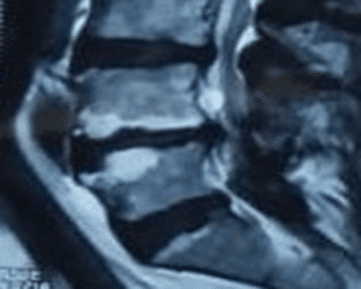

Rheumatology | Oct 16, 2024

Intradiscal Platelet-Rich Plasma Injection for Type I Modic Change Associated with Low Back Pain in Osteopenia

Low back pain (LBP) has the highest prevalence globally among musculoskeletal conditions and is the leading cause of disability worldwide....Read More